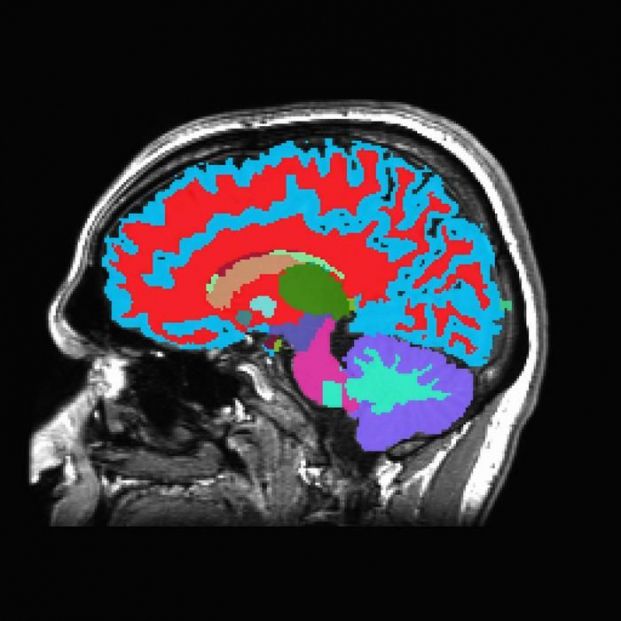

A partir de una sola resonancia magnética cerebral, la herramienta puede estimar el riesgo de padecer enfermedades crónicas en la mediana edad que suelen manifestarse décadas después. Esta información podría ayudar a motivar cambios en el estilo de vida y la alimentación que mejoren la salud. En las personas mayores, la herramienta puede predecir si alguien desarrollará demencia u otras enfermedades relacionadas con la edad años antes de que aparezcan los síntomas, cuando podrían tener una mejor oportunidad de retrasar el curso de la enfermedad.

La nueva herramienta, bautizada como DunedinPACNi, fue entrenada para estimar esta tasa de envejecimiento usando solo información de una única exploración por resonancia magnética del cerebro que se recopiló de 860 participantes del Estudio Dunedin cuando tenían 45 años. Luego, los investigadores la utilizaron para analizar escáneres cerebrales en otros conjuntos de datos de personas en el Reino Unido, Estados Unidos, Canadá y América Latina.